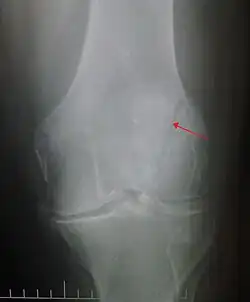

Some people have a normal bipartite patella or two-part patella which can appear as a fracture. The fragment is usually seen in the top outer corner of the patella and can be distinguished from a fracture by being present in both knees.[6]

The patella can break in various ways depending on the way it is injured, and into two or more pieces.[1] Types include transverse, the most common, with one fracture line;[5] marginal; osteochondral; and the rare vertical type, or stellate, where a direct compression force gives rise to a comminuted pattern.[5][7] Patella fractures can be further classified as displaced, where the broken ends of bone do not line up correctly and separate by more than 2mm, or undisplaced and stable where pieces of bone remain in contact with each other.[1][7] If fragments of patella bone stick out from the skin it is known as an open patella fracture, and closed if the overlying skin is intact.[1]

Vertical patella fracture